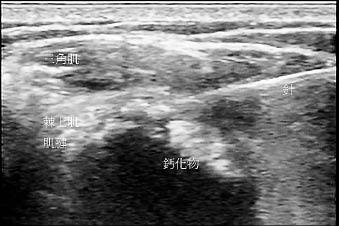

從上述的身體檢查,大致可推斷哪一條或哪幾條肌腱有問題,但要確定是否有鈣化性肌腱炎,需借助於影像檢查,如一般X光(圖1)、超音波(圖2)或磁振造影檢查。

穿刺或抽吸是在超音波的導引下,使用18至22號針頭多次穿刺或抽吸鈣化物,以加速鈣化物的排除(圖4)。